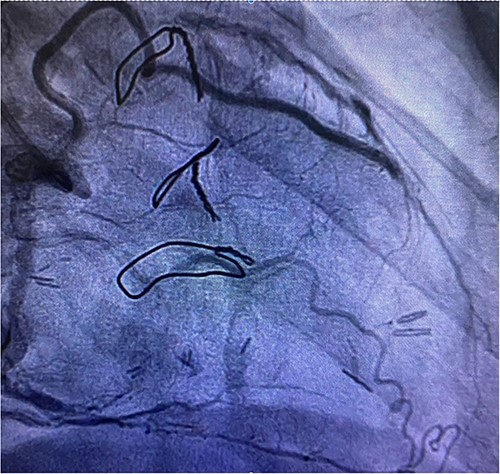

Before resternotomy, a cardiopulmonary bypass was performed via the right common femoral artery and vein. The RIMA was harvested in a semi-skeletonized fashion because skeletonized IMA is in general, longer than pedicled IMA. However, the RIMA could not reach the LAD in the present case due to cardiomegaly. Therefore, the proximal end of the RIMA was cut to use as a free graft. Subsequently, the proximal portion of the patent RA graft was tried to dissect as a proximal anastomosis site, but it was not possible due to severe adhesion of the surrounding tissue. Therefore, we decided to anastomose the proximal RIMA to the proximal right coronary artery (RCA) as the inflow site. The distal RIMA was anastomosed to the LAD as usual (Fig. 1). The postoperative course was uneventful, and the patient was discharged 11 days after the operation. A 3-month postoperative coronary angiogram showed the patency of the RA and RIMA conduits (Fig. 2). Moreover, from coronary computed tomography angiography after 6 years, it was confirmed that it was still patent (Fig. 3).

Post redoing coronary angiography showing patency of RIMA to LAD after 3 months.